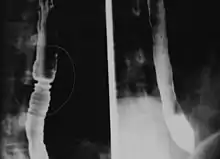

Radiologically, the term "ringed esophagus" has been used for the appearance of eosinophilic esophagitis on barium swallow studies to contrast with the appearance of transient transverse folds sometimes seen with esophageal reflux (termed "feline esophagus").[12]

Endoscopically, ridges, furrows, or rings may be seen in the esophageal wall. Sometimes, multiple rings may occur in the esophagus, leading to the term "corrugated esophagus" or "feline esophagus" due to similarity of the rings to the cat esophagus. Presence of white exudates in esophagus is also suggestive of the diagnosis.[13] On biopsy taken at the time of endoscopy, numerous eosinophils can be seen in the superficial epithelium. A minimum of 15 eosinophils per high-power field are required to make the diagnosis. Eosinophilic inflammation is not limited to the esophagus alone, and does extend through the whole gastrointestinal tract. Profoundly degranulated eosinophils may also be present, as may micro-abscesses and an expansion of the basal layer.[3][10]